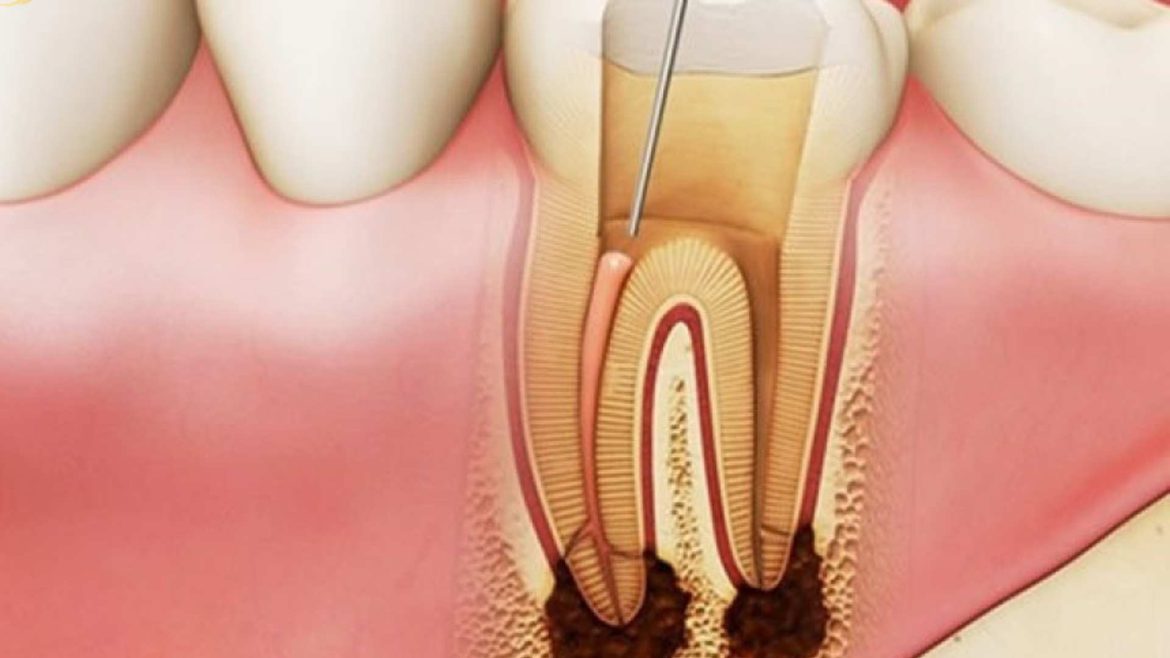

Sâu răng là bệnh lý răng miệng phổ biến, nếu ở mức độ nhẹ thì chưa cần thiết phải nhổ răng mà khi đó bác sĩ sẽ thực hiện phương pháp trám răng. Và chi phí cho dịch vụ này …